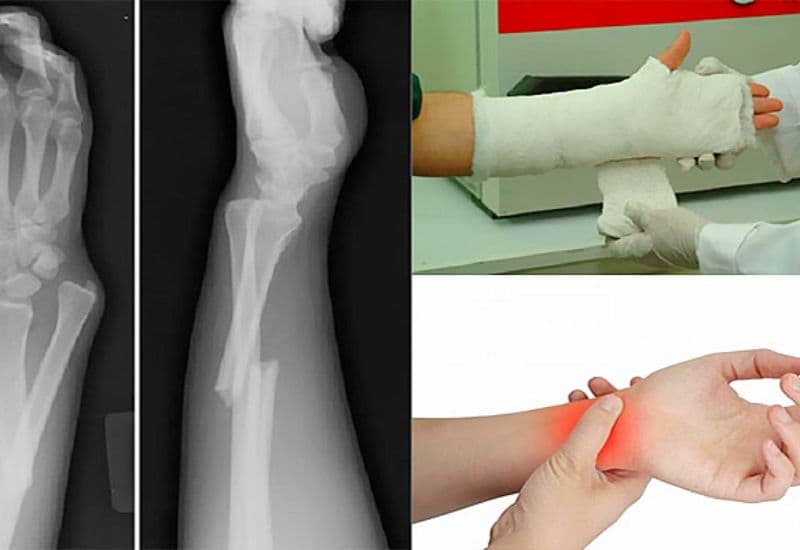

4.1 Chẩn đoán gãy xương cánh tay

Khi nghi ngờ bị gãy xương cánh tay, người bệnh nên đến bệnh viện để được chẩn đoán chính xác. Ban đầu, người bệnh sẽ được thăm khám với bác sĩ chuyên khoa ngoại hoặc ngoại cấp cứu, sau đó được chỉ định chụp chiếu để xác định chính xác vị trí, mức độ và loại hình tổn thương.

Chụp chiếu gồm:

– Chụp X-quang: Đây là phương pháp phổ biến nhất để xác định vị trí và mức độ gãy xương.

– Chụp CT: Đôi khi, bác sĩ có thể yêu cầu chụp CT để đánh giá chi tiết hơn về tình trạng xương.

Chụp X quang thường được áp dụng để chẩn đoán xác định vị trí và mức độ gãy xương, từ đó bác sĩ sẽ đưa ra phương pháp điều trị thích hợp.